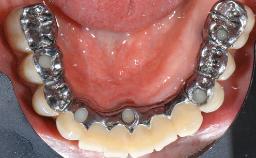

Oral Lichen Planus Associated with the Peri-implant Mucosa

This case describes the ongoing management of a 64-year-old healthy, non-smoking female patient with erosive oral lichen planus (OLP) affecting the gingivae and the buccal and lingual mucosa. The peri-implant mucosa was also affected subsequent to implant placement. The patient had osseointegrated implants (four in the maxilla, four in the mandible) placed following extraction of hopeless teeth and a healing period. The patient had a history of OLP prior to implant placement and had been referred to an oral-medicine specialist for definitive diagnosis and treatment. She exhibited generalized oral mucosal involvement. Following a clinical assessment, biopsy, and blood tests, she was treated with topical corticosteroids. Systemic prednisolone was reserved for severe flare-ups. Amphotericin lozenges were used in combination with corticosteroid treatment to prevent the development of oral candidiasis.

# of Implants 8

Type of Implants Two-Piece

Prosthesis Type FDP